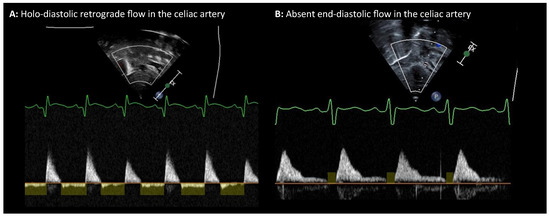

The management of patent ductus arteriosus (PDA) in premature infants remains a significant debate in neonatology. Interventions aimed at accelerating ductal closure, often using nonsteroidal anti-inflammatory drugs (NSAIDs) or acetaminophen, are common practice. However, recent evidence increasingly challenges this approach. Pharmacological agents for [...] Read more.

The management of patent ductus arteriosus (PDA) in premature infants remains a significant debate in neonatology. Interventions aimed at accelerating ductal closure, often using nonsteroidal anti-inflammatory drugs (NSAIDs) or acetaminophen, are common practice. However, recent evidence increasingly challenges this approach. Pharmacological agents for PDA closure demonstrate limited efficacy and carry significant risks of systemic toxicity, affecting renal, gastrointestinal, vascular, and pulmonary systems. Multiple recent randomized controlled trials (RCTs) and meta-analyses have largely failed to demonstrate that early active treatment improves crucial clinical outcomes such as mortality, bronchopulmonary dysplasia (BPD), intraventricular hemorrhage (IVH), or necrotizing enterocolitis (NEC). Some studies even suggest potential harm, particularly an increased risk of BPD and mortality in vulnerable extremely preterm infants. Procedural closure methods (surgical ligation, transcatheter techniques), while achieving anatomical closure, also pose significant risks and lack evidence of improved clinical outcomes. Given the high rates of spontaneous PDA closure, especially in extremely preterm infants, and the lack of proven benefit alongside potential harm from interventions, a paradigm shift towards expectant or conservative management is gaining support. This approach emphasizes supportive care, minimizing interventions, and may be complemented by the judicious use of postnatal corticosteroids in selected infants with significant lung disease, which might indirectly facilitate ductal closure by addressing underlying inflammation. Full article